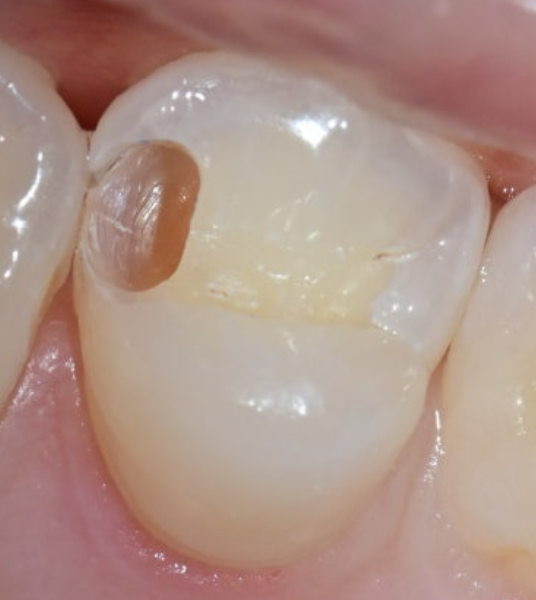

1️⃣ 큐레이로 충치 조기 진단

→ 겉은 멀쩡해 보여도 내부는 부드럽고 갈색으로 변질

2️⃣ 충치 완전 제거→ 아래에 단단한 치질만 남기고,

신경 보호를 위해 MTA or GI 사용